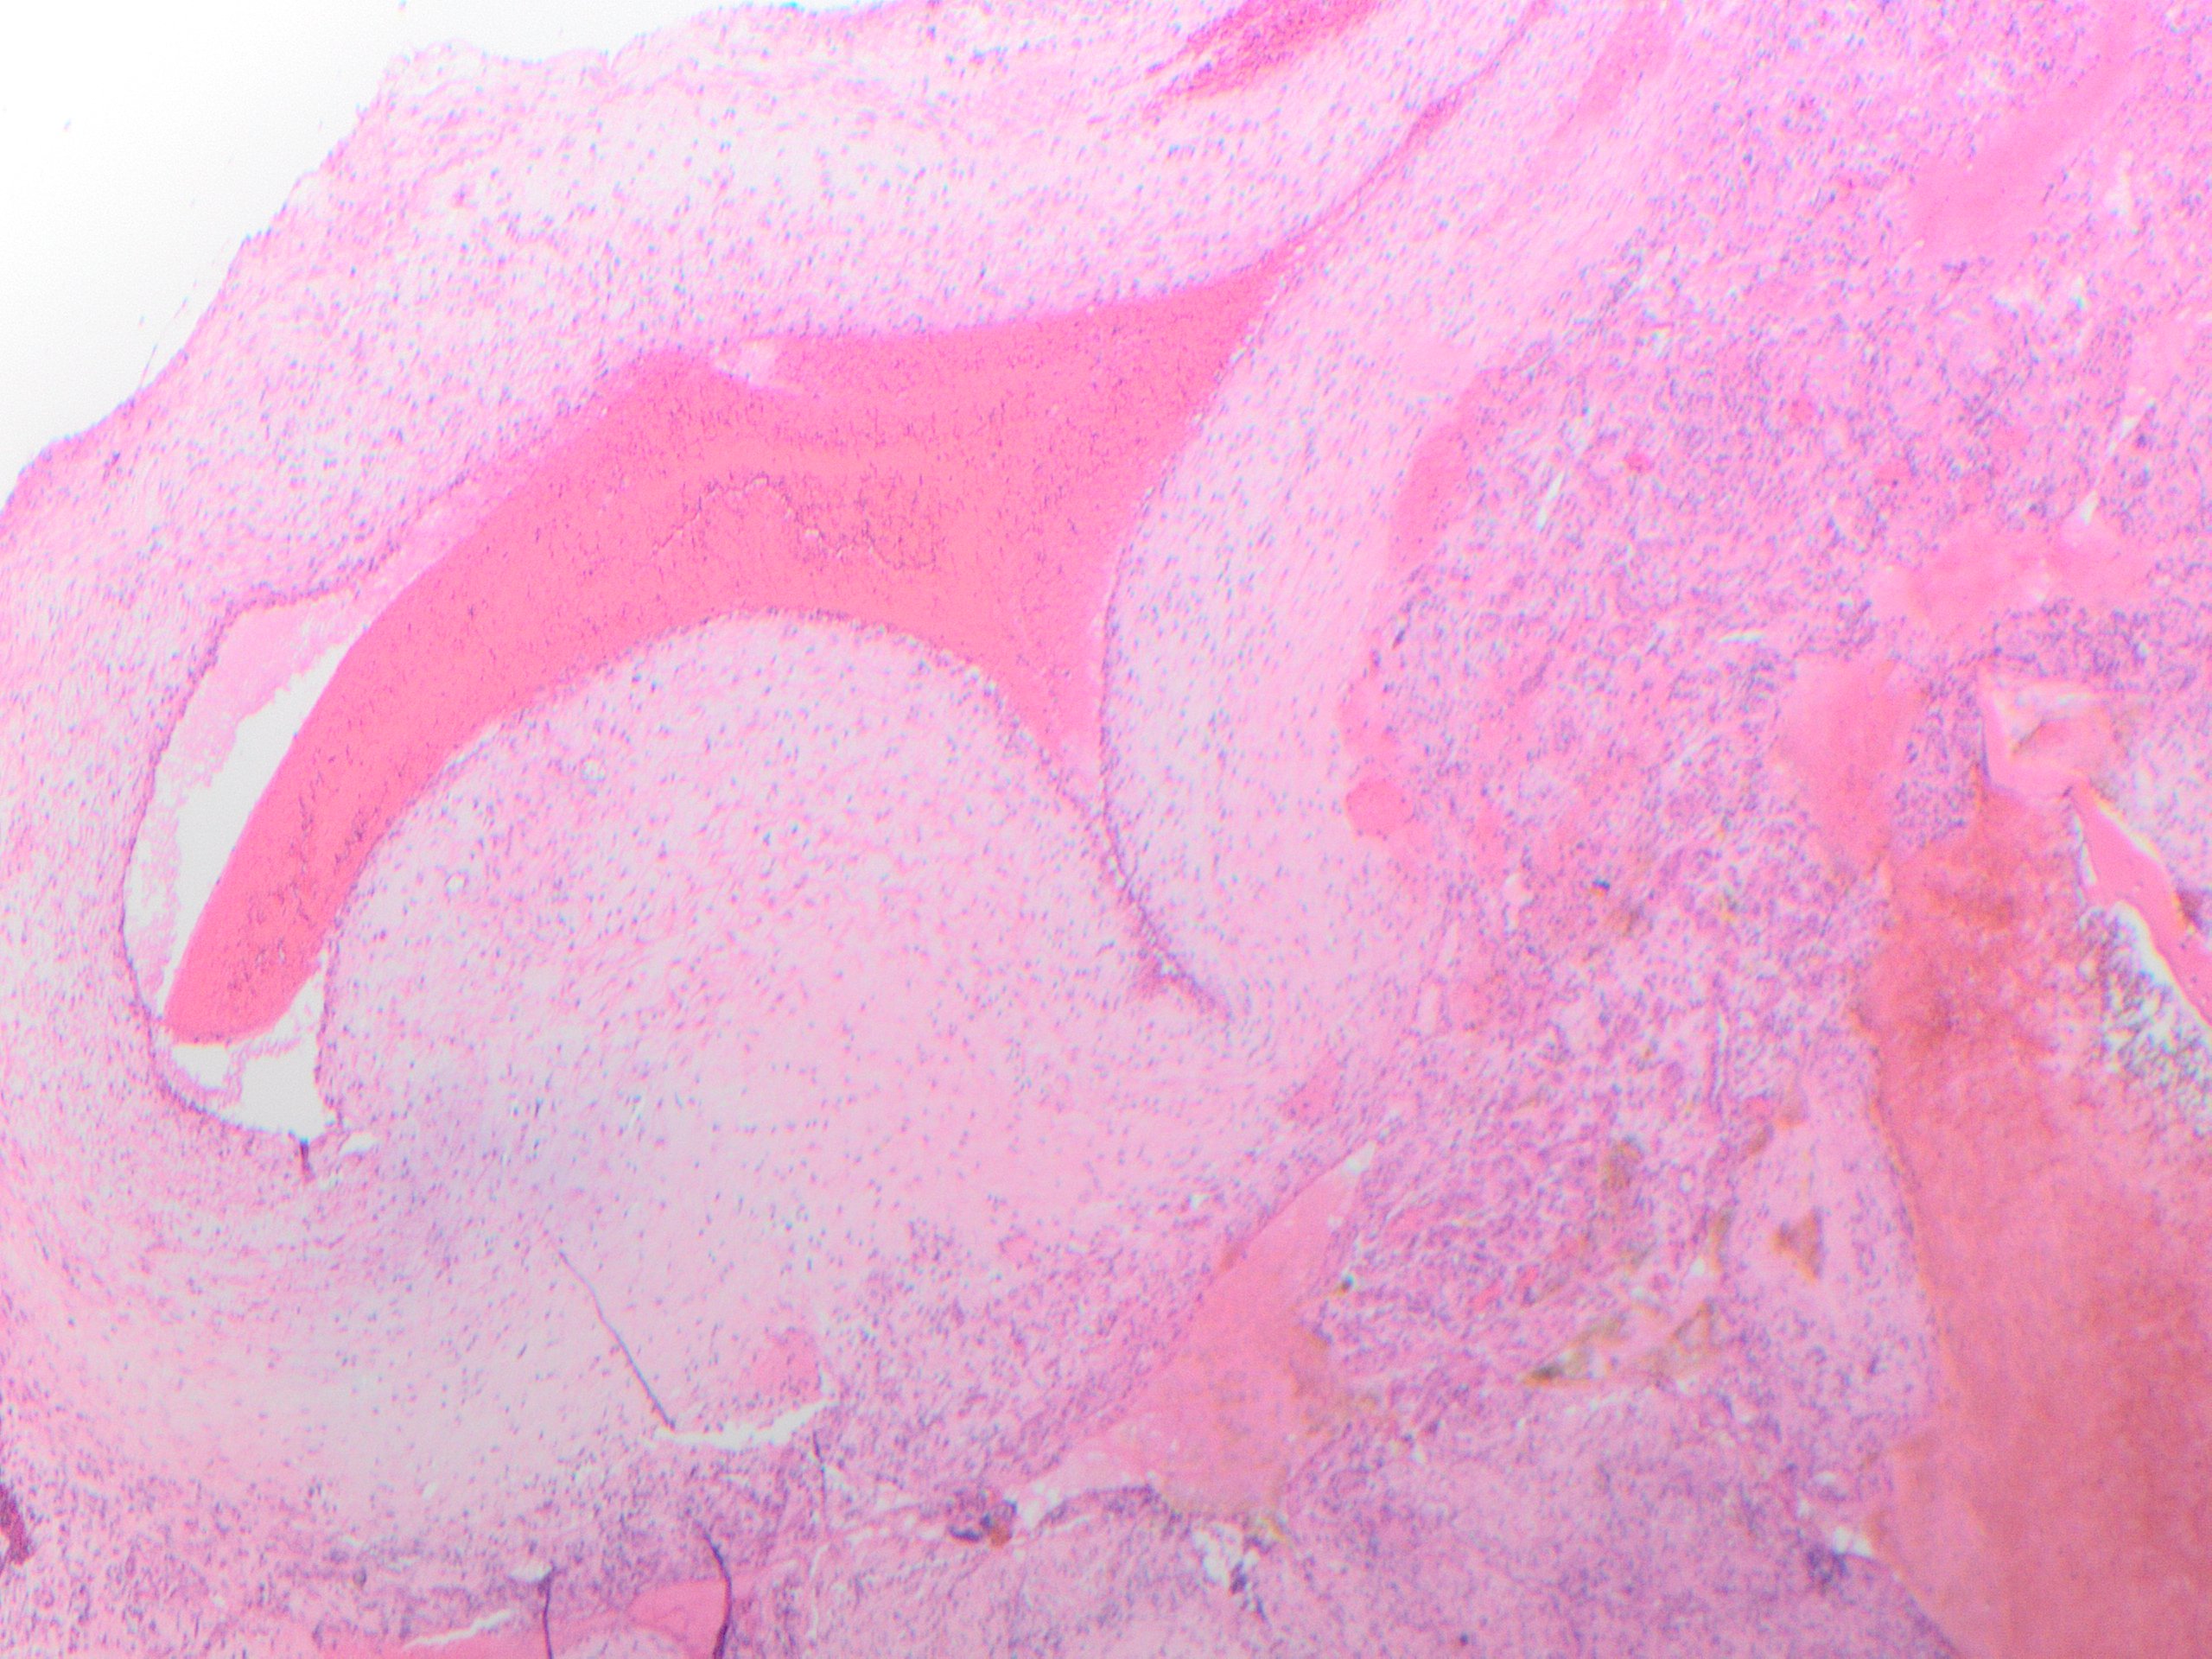

Microscopic sections show a proliferation of well-formed small blood vessels with lobular arrangement and occasionally arranged around small arteries. The small vessels are formed by epithelioid endothelial cells that display abundant eosinophilic cytoplasm and enlarged round nuclei, and normal to low nuclear-to-cytoplasmic ratio; while in more cellular areas the nuclei become elongated. The stroma is hemorrhagic to edematous with mixed inflammatory cells including numerous eosinophils, which may be a clue to the diagnosis in small biopsies.

The tumor cells express endothelial markers such as CD31, CD34, FLI1, ERG and factor VIII-related antigen. In this case, immunohistochemistry was used to demonstrate that the epithelioid endothelial cells were positive for the vascular marker ERG. Most cases show rearrangement of FOS or FOSB. The histopathologic differential diagnosis should include angiosarcoma, which is not typically well demarcated, lacks the lobular architecture, shows more cytologic atypia, and has significant proliferative activity (absent in this case). Metastatic carcinoma is negative for vascular markers. Epithelioid hemangioendothelioma shows hyalinized or chondroid stroma and vacuolated cells